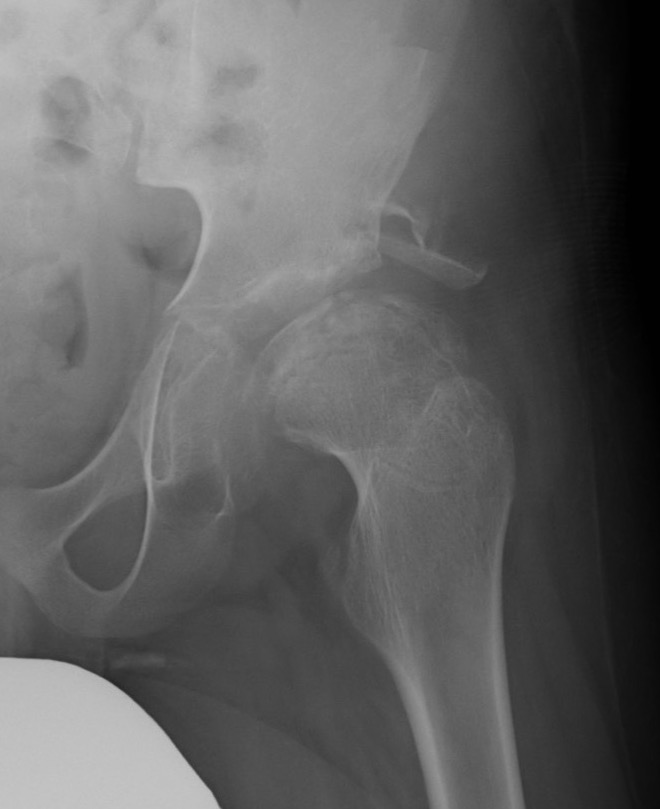

Issues

Persisting cova vara

Leg length discrepancy

Over-riding greater trochanter

Outcomes

- 52 Perthes patients treated with FVO

- optimal correction 15 degrees

- 30% had over riding greater trochanter

- 37% no correction of varus over time

Beer et al J Pediatr Orthop 2008

- 43 hips treated with FVO with 33 year follow up

- 55% Stuhlberg I / II

- 42% Stuhlberg III / IV

- 2% Stuhlberg V